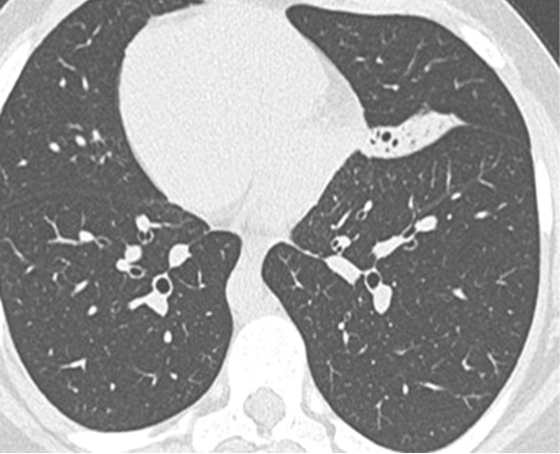

Le syndrome de Kartagener est une affection héréditaire rare de transmission autosomique récessive. Il se caractérise par une triade: bronchectasies, rhinosinusite chronique et situs inversus. L'évolution est dominée par la survenue d'infections respiratoires haute et basses. Patiente âgée de 21 ans, admise pour obstruction nasale bilatérale, hyposmie et rhinorrhée évoluant depuis 3 ans. Elle présentait depuis le jeune âge des broncho-pneumopathies à répétition non explorées. L'examen physique a retrouvé des râles bronchiques bilatéraux, des bruits de cœur plus bien perçus du côté droit, une rhinorrhée purulente avec muqueuse nasale congestive, des cornets moyens hypertrophiés et des polypes translucides comblant les 2 méats moyens. L'otoscopie a objectivé des tympans complets rétractés. Le bilan biologique a révélé une anémie hypochrome microcytaire. L'audiométrie tonale a montré une surdité de transmission bilatérale à 40 dB. A l'impédancemétrie, les courbes étaient déviées vers les pressions négatives et les réflexes stapédiens étaient absents. La radiographie du thorax a montré une dextrocardie. La TDM du massif facial et thoracique a montré un comblement des sinus maxillaires, des cellules ethmoïdales, et un situs inversus sans anomalies des gros vaisseaux. L'échographie abdominale n'a pas montré de transposition de viscères. Le traitement médical s'est basé sur la prescription d'antibiotiques et de corticoïdes par voie locale et générale, associée à une kinésithérapie respiratoire. Le traitement chirurgical a consisté en une polypectomie, méatotomie moyenne bilatérale et mise en place de 2 drains trans-tympaniques. L'évolution était marquée par une nette amélioration clinique avec un recul de 7 ans.